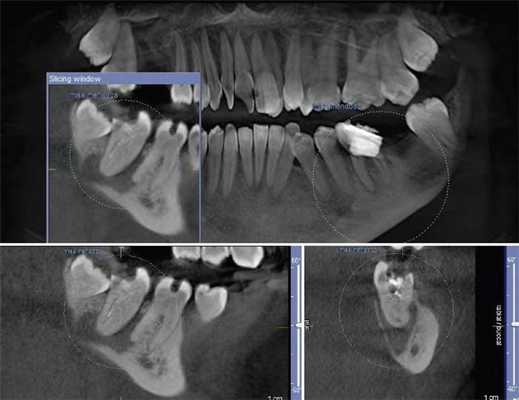

КЛКТ используется в стоматологии начиная с 1981 года. В отличие от обычного КТ, которое создает изображение на разных слоях, КЛКТ создает изображение в 3D пикселях называемых воксель. Так как эти воксели являются изотропичными, объект тщательно измеряется в различных направлениях. Это позволяет визуализировать геометрически неискаженное изображение челюстно-лицевой области, которое возможно просматривать при разных углах. Вдобавок для обеспечения высокого разрешения изображения, КЛКТ доступно для просмотра с разных точек (FOV) для применения в различных ситуациях. В эндодонтии аппарат с ограниченным FOV обычно является достаточным. Обычно, чем меньше объем скана, чем выше пространственное разрешение изображения. Так как ранний симптом периапикальной патологии это прерывистость твердой пластинки и расширение периодонтальной щели, оптимальным разрешением при получении КЛКТ изображения, применяемом в эндодонтии, не должно превышать 200 нм - средняя ширина периодонтального пространства. 3D Accuitomo (K Morita, Corporation, Kyoto, Japan) - первая из малых FOV систем - обеспечивает разрешение в 0,125 мм. Orthophos XG3D (Sirons Germany) также обеспечивает получение FOV 5*5 специально для эндодонтических целей.

Ramamurthy и Matherene описывают ограниченность 2D изображений для определения MB2 каналов (Фото 1).

Фото 1: изображение MB2 в обоих первых молярах

Наиболее частым патологическим состоянием, затрагивающим зубы является воспалительные процессы пульпы и периапикальных областей. Технология КЛКТ теперь предоставляет клиницисту возможность обозревать нужную зону в трех различных плоскостях, тем самым получая 3D информацию. Поражения, заключенные в губчатом веществе кости с малым количеством или отсутствием кортикальной пластинки, на обычной пленке могут быть диагностированы с большим трудом. Lofthag-Hansen, Stavropoulos и Wenzel сравнили точность получаемых данных при КЛКТ с ограниченным FOV и обычными снимками.

Ученые сообщили, что КЛКТ предоставляет более точные диагностические данные (61%) по сравнения с цифровыми (39%) и обычными (44%) рентгенограммами. Но, несмотря на то, что данные КЛКТ являются более точными, исследователи не призывают к полному вытеснению обычной внутриротовой рентгенографии для выявления периапикальных изменений в обычной клинической практике из-за финансовой и вредностной составляющих. Estrela и коллеги предложили использовать периапикальные индексы, основанные на КЛКТ, для идентификации патологий (Фото 4-6).

Фото 4: Периапикальная киста в переднем сегменте нижней челюсти

А: 3D изображение, показывающее большую кистозную полость

B: Изображение секционного распила, показывающее утрату кортикальной пластинки

C: Аксиальный вид, демонстрирующий утрату кортикальной пластинки с лабиальной стороны и интактную пластинку с лингвальной.

Фото 5: Хронические периапикальные абсцессы около первого правого нижнего моляра

Фото 6: Поражение периодонтальных тканей около левого верхнего второго моляра